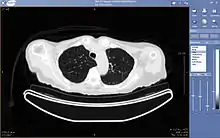

Teleradiology is the transmission of radiological patient images from procedures such as x-rays photographs, Computed tomography (CT), and MRI imaging, from one location to another for the purposes of sharing studies with other radiologists and physicians. Teleradiology allows radiologists to provide services without actually having to be at the location of the patient. This is particularly important when a sub-specialist such as an MRI radiologist, neuroradiologist, pediatric radiologist, or musculoskeletal radiologist is needed, since these professionals are generally only located in large metropolitan areas working during daytime hours. Teleradiology allows for specialists to be available at all times.

Teleradiology utilizes standard network technologies such as the Internet, telephone lines, wide area networks, local area networks (LAN) and the latest advanced technologies such as medical cloud computing. Specialized software is used to transmit the images and enable the radiologist to effectively analyze potentially hundreds of images of a given study. Technologies such as advanced graphics processing, voice recognition, artificial intelligence, and image compression are often used in teleradiology. Through teleradiology and mobile DICOM viewers, images can be sent to another part of the hospital or to other locations around the world with equal effort.[1]